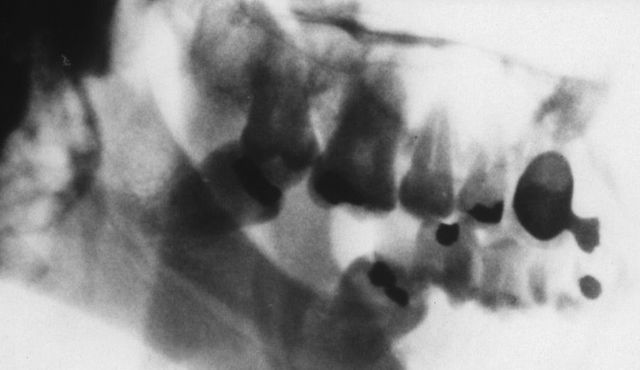

Dokumente des Grauens: Röntgenaufnahmen von Folteropfern

Hermann Vogel: Fotos von Folteropfern sind oft so brutal und direkt, dass der Betrachter reflexartig wegschaut. Anonyme Röntgenbilder sind besser auszuhalten. Zunächst erkennt der Betrachter nur, dass ein Finger fehlt oder ein Knochen zerbrochen ist. Das weckt sein Interesse und er will erfahren, was dem Menschen passiert ist. Die Bilder führen also dazu, dass sich die Menschen mit dem Thema Folter beschäftigen – auf erträgliche Weise. Und genau das ist mein Ziel.

Sie entlarven von außen nicht erkennbare Verletzungen, somit auch Spuren von Folter. Eine gerichtsmedizinische Untersuchung macht Frakturen, eingeführte Fremdkörper, Nadeln sichtbar. Die Aufnahmen ermöglichen eine Plausibilitätsprüfung. Stimmen die Schilderungen des Opfers mit dem Verletzungsmuster überein? Stimmt das Alter der Verletzung überein mit dem Zeitraum, den die Person für die erfahrene Folter angibt? Entspricht die Foltermethode dem, was für die angegebene Region und die verantwortliche Organisation, Militär oder Miliz, bekannt ist?